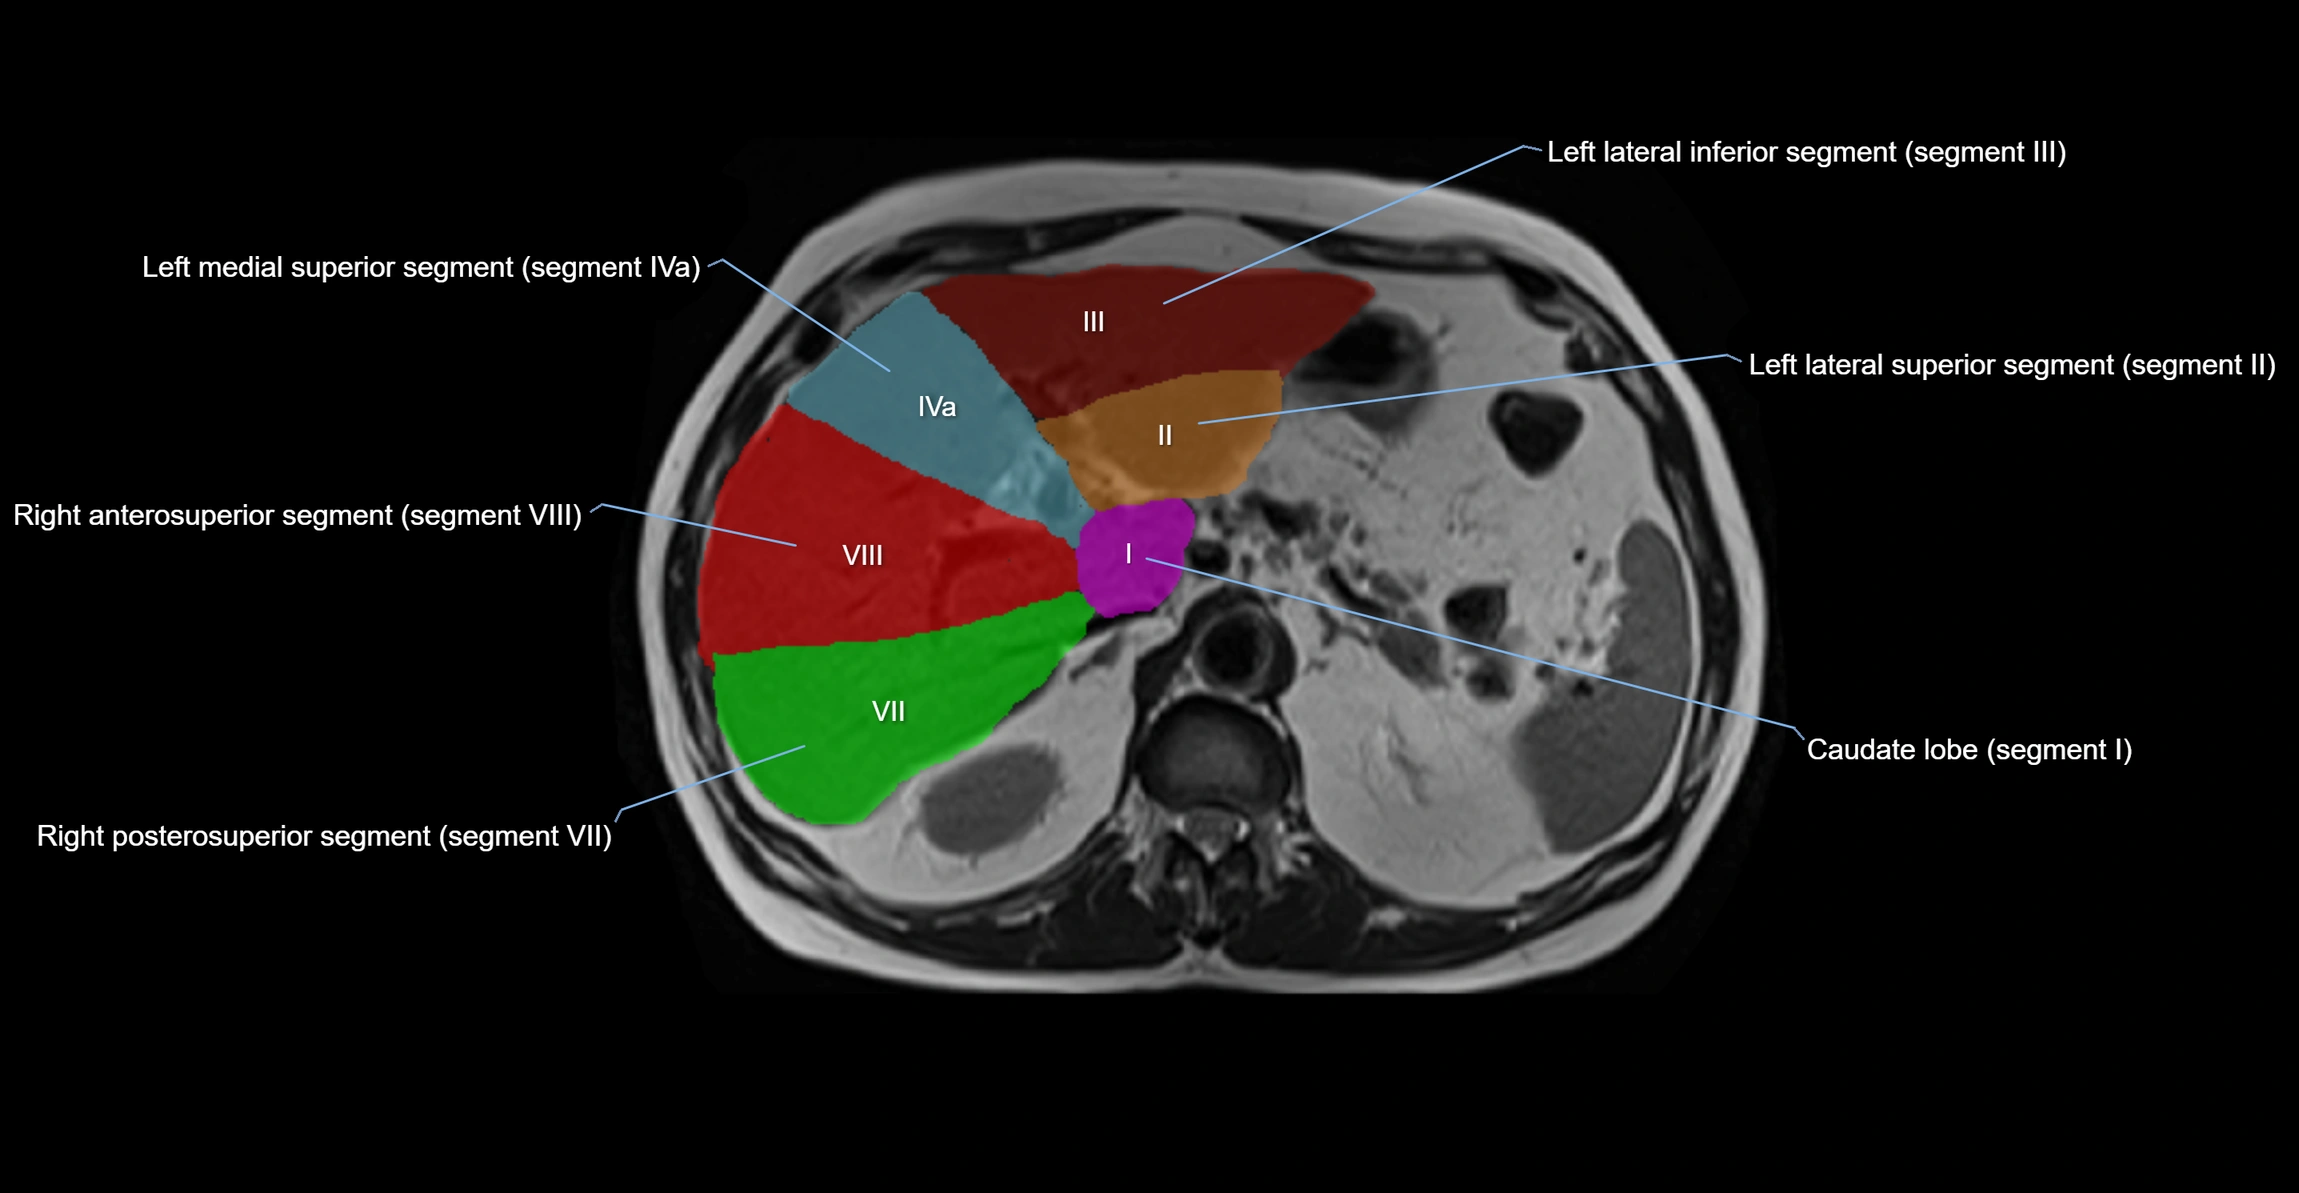

The caudate lobe of the liver is a distinct anatomical subdivision of the liver, designated as segment I in Couinaud’s classification. It lies on the posterior surface of the liver, between the fissure for the ligamentum venosum (left boundary) and the groove for the inferior vena cava (IVC) (right boundary). Superiorly, it is related to the posterior liver surface, and inferiorly it is separated from the left lobe by the porta hepatis.

The caudate lobe is unique because it receives dual portal venous and arterial inflow from both the right and left portal veins and hepatic arteries. It also has independent venous drainage directly into the IVC via multiple small hepatic veins, unlike other lobes that drain through the three main hepatic veins.

• Segment I (Couinaud classification)